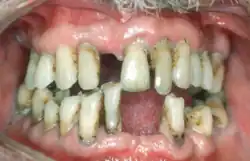

Periodontal disease, also known as gum disease, is a set of inflammatory conditions affecting the tissues surrounding the teeth.[5] In its early stage, called gingivitis, the gums become swollen and red and may bleed.[5] It is considered the main cause of tooth loss for adults worldwide.[7][8] In its more serious form, called periodontitis, the gums can pull away from the tooth, bone can be lost, and the teeth may loosen or fall out.[5] Halitosis (bad breath) may also occur.[1]

| Symptoms | Red, swollen, painful, bleeding gums, loose teeth, bad breath[1] |

| Complications | Tooth loss, gum abscess[1][2] |